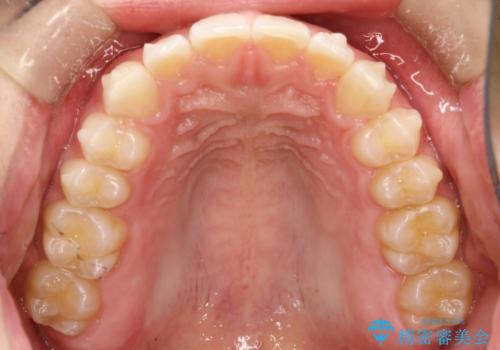

前歯の隙間がきになる インビザラインですきっ歯の治療

- 上の前歯の隙間を主訴に来院されました。

正中に隙間があり、かみ合わせが深い過蓋咬合という状態でした。

インビザラインにて矯正治療を行いました。